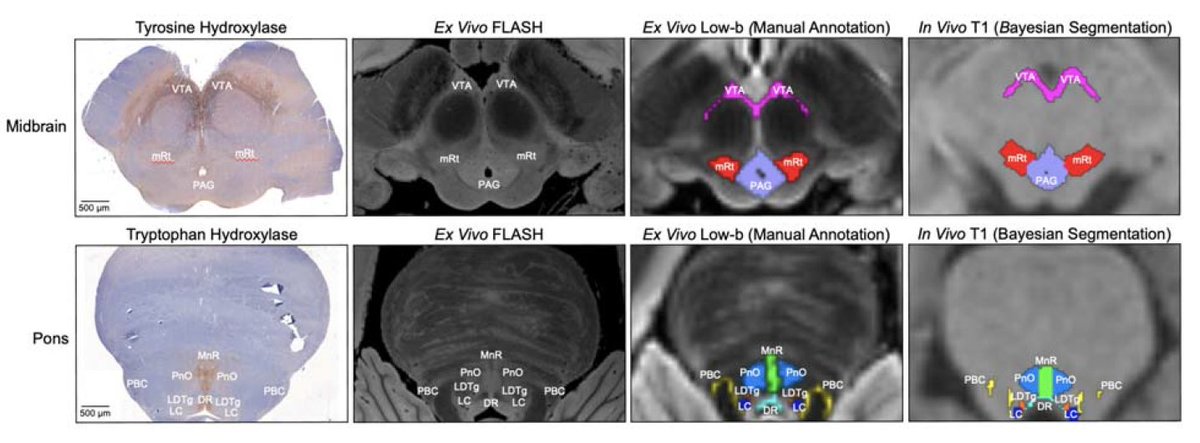

脳幹覚醒核研究のために750μmの等方性解像度で5つの生体外ヒト脳標本の拡散MRIを基に、上行性網様体賦活系(AAN)核の高精度なprobablistic atlasとBaise推定に基づく自動segmentation toolを開発 FreeSurferに実装予定とのこと #soft #pons #papers doi.org/10.1101/2024.0…

thmonk_pf's tweet image. 脳幹覚醒核研究のために750μmの等方性解像度で5つの生体外ヒト脳標本の拡散MRIを基に、上行性網様体賦活系(AAN)核の高精度なprobablistic atlasとBaise推定に基づく自動segmentation toolを開発

FreeSurferに実装予定とのこと